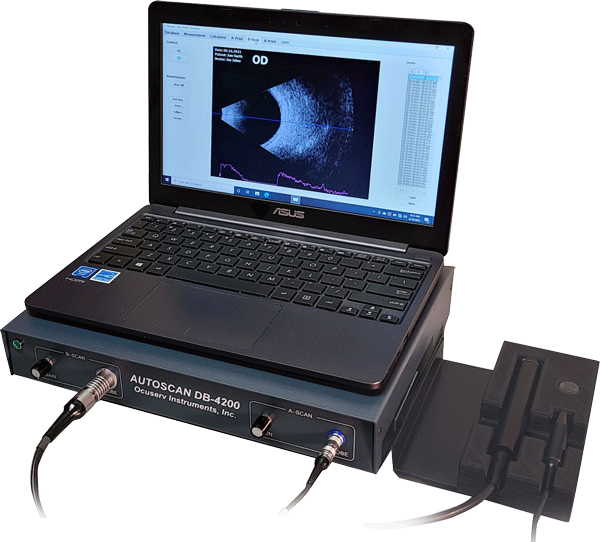

B-Scan

- Exceptional signal to noise ratio yields a deep penetration while maintaining high resolution image.

- 10 MHz transducer and 55 degrees of viewing angle with 256 scan lines produces a high quality sonogram.